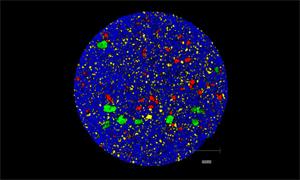

- Generate images of the formulations used in tablets, inhalers and nasal sprays at sub-micrometre spatial resolution

- Fast, quantitative analyses of entire tablets and powder blends

- Determine the uniformity of mixing

Rapidly generate images of your formulations with StreamLine™. This uses line focus illumination, allowing you to use higher laser powers without risk of sample damage, thereby reducing experiment times.

Generate images of formulations

Ensure your chemical images are representative; use Renishaw's StreamLine. You can change resolution to suit your domain size and, because Renishaw's WiRE software can cope with massive data files, you can analyse over the entire sample surface. Powerful Renishaw features, such as Slalom (to ensure the whole surface is sampled) and HD imaging (to get crisp clear images), provide all the options you need, whatever your formulation.